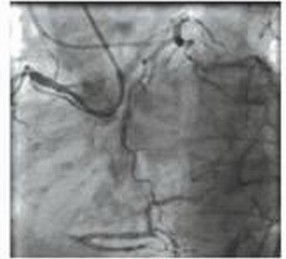

有时钢丝通过病变后不能确定其走行在真假腔,或者钢丝不能找到真腔,此时可以在IVUS指导下穿刺内膜,确定真腔走向(图3)。